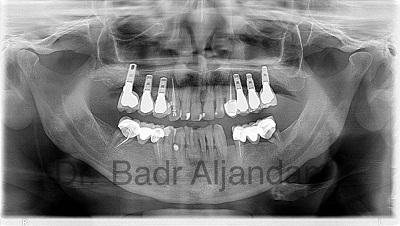

After the implant has bonded to the jawbone, the second phase begins. Dr. Al-jandan will uncover the implants and attach small posts that protrude through the gums and will act as anchors for the artificial teeth. When the artificial teeth are placed, these posts will not be seen. The entire procedure usually takes six to eight months. Most patients experience minimal disruption in their daily life.

Dental Implant placement is a team effort between an oral and maxillofacial surgeon and a restorative dentist. While Dr. Al-jandan performs the actual implant surgery, initial tooth extractions, and bone grafting if necessary, the restorative dentist (your dentist) fits and makes the permanent prosthesis. Your dentist will also make any temporary prosthesis needed during the implant process.

A single prosthesis (crown) is used to replace one missing tooth – each prosthetic tooth attaches to its own implant. A partial prosthesis (fixed bridge) can replace two or more teeth and may require only two or three implants. A complete dental prosthesis (fixed bridge) replaces all the teeth in your upper or lower jaw. The number of implants varies depending upon which type of complete prosthesis (removable or fixed) is recommended. A removable prosthesis (over denture) attaches to a bar or ball in socket attachments, whereas a fixed prosthesis is permanent and removable only by the dentist.

Dr Al-jandan performs in-office implant surgery in a hospital-style operating suite, thus optimizing the level of sterility. Inpatient hospital implant surgery is for patients who have special medical or anesthetic needs or for those who need extensive bone grafting from the jaw, hip or tibia.